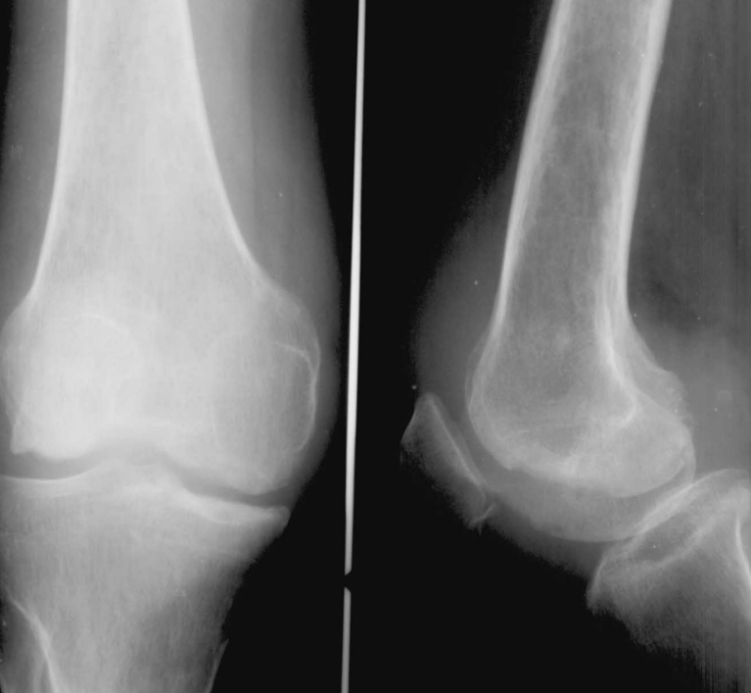

骨巨细胞瘤(GCT)

临床与病理:1、年龄:20-40岁,约65%;2、部位:长管状骨骨端,膝关节附近居多

X线表现:① 多数为偏心性骨破坏 (溶骨型)② 局部骨 膨胀性,骨皮质变薄形成薄层骨壳,无硬化边③ 大小不一的分隔小房呈肥皂泡状, 并见骨嵴。

④ 无骨膜反应,⑤一般不穿破关节软骨

桡骨远端偏侧性膨胀性骨质破坏,中有骨嵴。